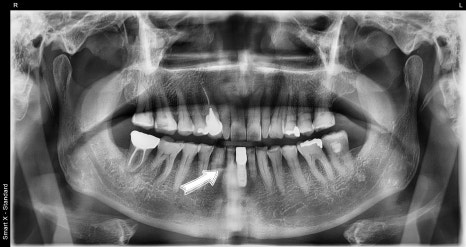

The post-surgery X-ray showed that the implant had settled stably,

and the surrounding bone condition was being maintained well.

The patient had almost no pain immediately after surgery,

and after treatment, was able to return to daily life without discomfort in eating or speaking.